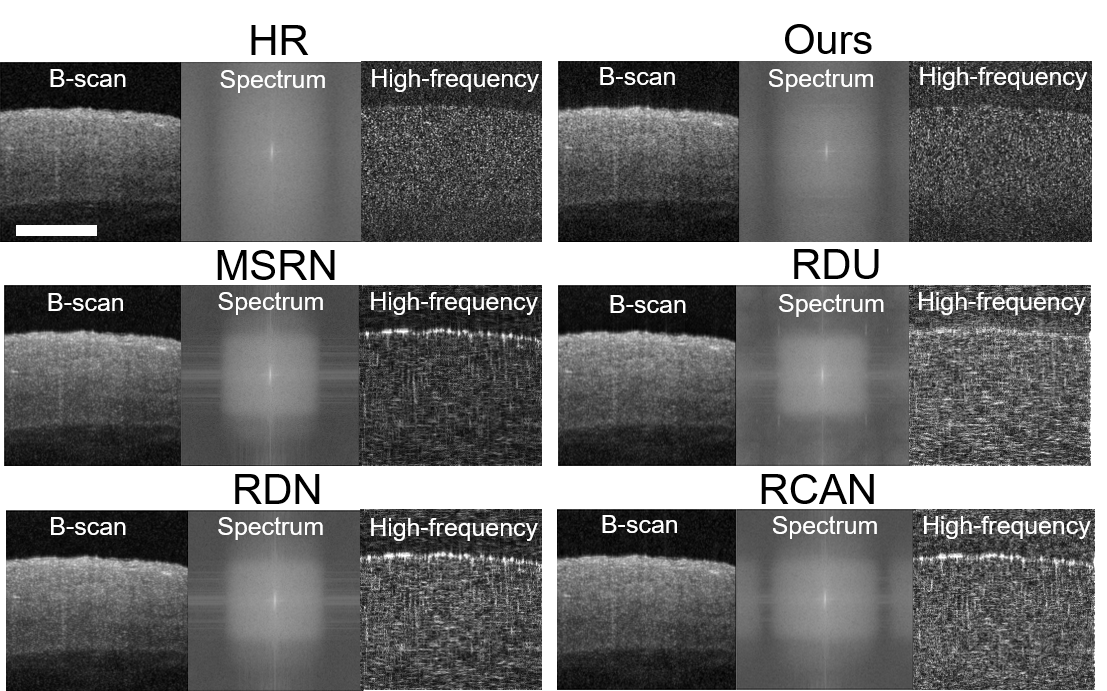

However, the current DL research in generating SR OCT images focuses solely on the spatial distribution of pixels in B-scans, without consideration of frequency information. The lack of frequency-awareness poses limitation on SR performance in two aspects. Firstly, from 1-D frequency perspective, SDOCT is physically measured in spectrum and reconstructed in spatial domain. Considering frequency information along axial direction would increase the fidelity of reconstruction. Secondly, from 2-D image processing perspective, current DL models exhibit spectral bias, which is a learning bias towards low-frequency components [26, 27]. As shown in Fig 1, DL algorithms induce frequency domain gaps in SR OCT images compared to the reference HR images, as they fail to resemble the high-frequency components, such as edges and textures of the coronary artery sample. High-frequency components preserve finer details that are beneficial for medical imaging [28]. Therefore, a DL framework with frequency awareness is needed to reduce spectral bias and generate high-quality SR OCT images.

3.6 Analysis on spectral bias

We perform frequency analysis to evaluate the spectral bias of our frequency-aware model and other DL algorithms. We apply 2D DFT to the HR and SR OCT images, after which we average the logarithm of the intensities for each A-line and plot the intensity values over the pixels. The frequency analysis is carried out by averaging the spectrum of the SR OCT images. The results are reported in Fig 3. As shown in Fig 3 (a), our frequency-aware model generates SR images with averaged spectrums that are similar to the HR images. The summed intensities for pixels, as shown in Fig 3 (b), confirm our frequency-aware model are less biased in spectrum distribution compared with other DL algorithms. On the other hand, existing DL algorithms generate SR OCT images with spectral bias in an unstable manner, as confirmed by Fig 3.